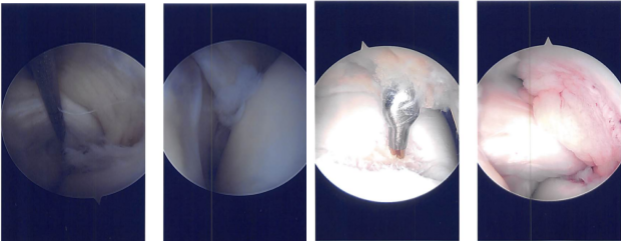

The patellofemoral joint was checked. The posterior surface of the patella was pristine, but there was a large grade 3 to grade 4 osteochondral lesion in the trochlea.

Lateral meniscus showed a tear in the posterior body of the lateral meniscus vertical radially oriented up to the periphery. There was a grade 1 to grade 2 osteochondral lesion on the lateral femoral condyle also.

Intraoperative Arthroscopy Images

A medial entry portal was made with direct access to the lateral meniscus. A shaver and upbiters were Introduced and the meniscectomy was performed as the meniscus was not amenable to repair. A stable margins were reached. The chondroplasty of the lateral femoral condyle was done.

The chondroplasty of the trochlea was also done and considering it to be a grade 4 lesion. A microfracture was performed. Fat globules could be seen coming out. Dressing was done. The patient was moved to the holding area from the postoperative care unit in a stable condition after extubation.